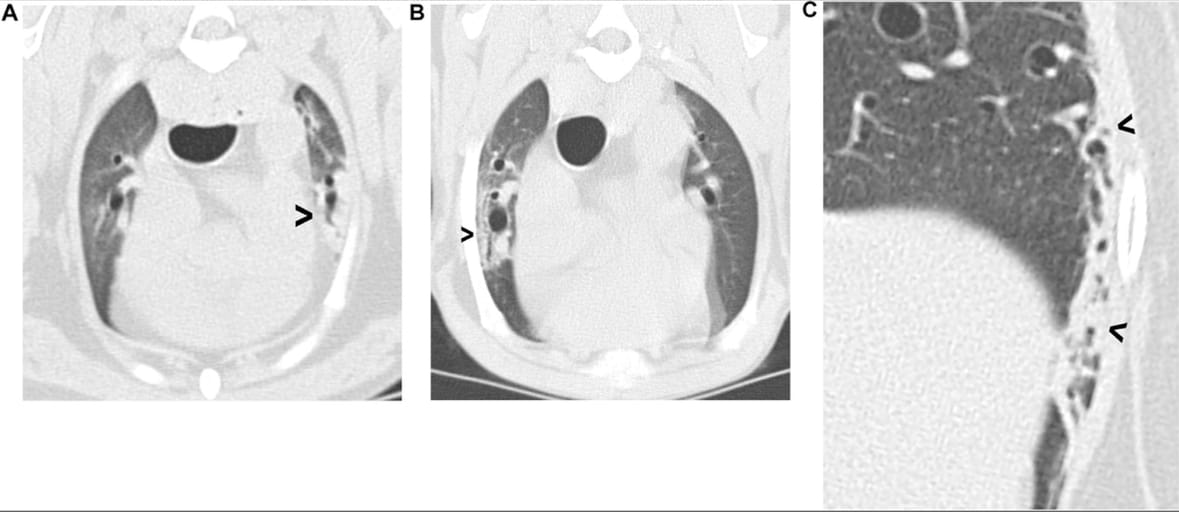

Examples of pulmonary collapse. (A) Collapse of the ventral tip of the left cranial lobe (arrowhead); (B) bronchocentric collapse (arrowhead) affecting the right cranial lobe; (C) peripheral pulmonary collapse (arrowheads) affecting the lateral aspect of the left caudal lobe